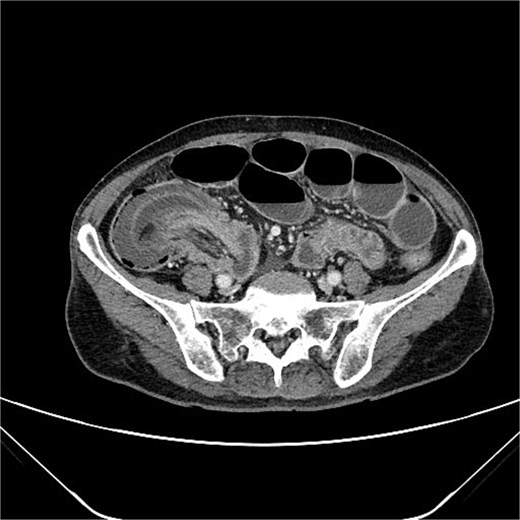

A 76-year-old female patient presented to the emergency department with abdominal pain and vomiting. A standard radiography (Fig. 1) and a contrast-enhanced abdominal CT scan revealed an intestinal obstruction caused by intussusception of the terminal ileum into the cecum (Figs 2 and 3). Laboratory tests showed elevated C-reactive protein levels and leukocytosis. Her medical history was significant for bilateral carotid artery stenosis (under treatment with clopidogrel), mild obstructive sleep apnea syndrome, and hypertension.

The patient exhibited classical symptoms of bowel obstruction (abdominal pain and vomiting), confirmed by imaging studies. The elevation of inflammatory markers suggested a more advanced disease stage, possibly with localized inflammation or ischemia. The patient’s prior medical history did not directly influence the intussusception, but these comorbidities required careful perioperative management. The CT scan clearly demonstrated intussusception of the terminal ileum into the cecum, which is consistent with an ileocolic intussusception, a relatively common form in adults. Given the clinical and radiological findings, the patient underwent urgent laparoscopic right hemicolectomy with extracorporeal anastomosis.

Intussusception is described as the telescoping of one bowel segment with its mesenteric fold into an adjoining bowel tract, causing venous congestion and blood supply reduction. Intussusception can occur anywhere along the small and large bowel. This condition in adults poses diagnostic and therapeutic challenges due to its rarity and the nonspecificity of symptoms. Most adult cases are associated with an underlying lesion, often neoplastic, benign [8] or malignant (metastatic lesions, lymphomas, and adenocarcinomas), which underscores the importance of surgical resection and histological analysis [5]. The use of contrast-enhanced CT has greatly improved the preoperative diagnosis of intussusception, allowing for early and accurate identification of the condition. CT scan shows a peculiar sign, described either as “target,” “bulls- eye,” or “sausage-shaped” lesion (Fig. 3). This pathognomonic sign can be identified at coronal and axial view [5]. This case emphasizes the need for a high index of suspicion in elderly patients presenting with bowel obstruction and nonspecific abdominal symptoms. Prompt surgical intervention, as performed in this case, is crucial to prevent complications such as bowel ischemia or perforation, which significantly increase morbidity and mortality. Moreover, in this case, an underlying potentially malignant evolving condition was discovered and removed. Given the patient’s overall clinical status and the urgency of the situation, the choice of surgical management was appropriate.